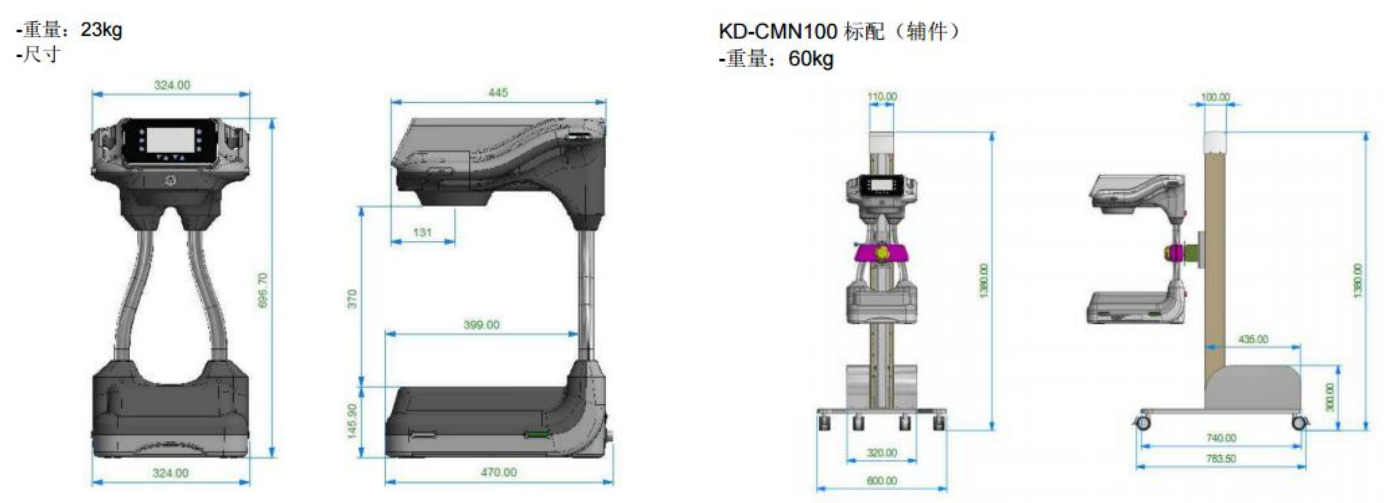

紧凑灵活的台式C臂结构设计

便捷、精巧、灵活是 CMN100 带给用户最直观的体验和感受。 从整机的结构设计以及占地和重量考虑,均立足于手足外科的临床应用需要。

紧凑的设计强化设备的流动性、通用性和灵活性

紧凑的 MINI C 臂设计,比普通 C 形臂移动性能更好,方便患者的检查并提高被检对象的流动性;

简易的操作流程和 83KG 的整机重量,普通大夫或护士单人即可驱动操控;

不足 1 平米的空间占地,可以自由穿梭在手术室间甚至病床旁。